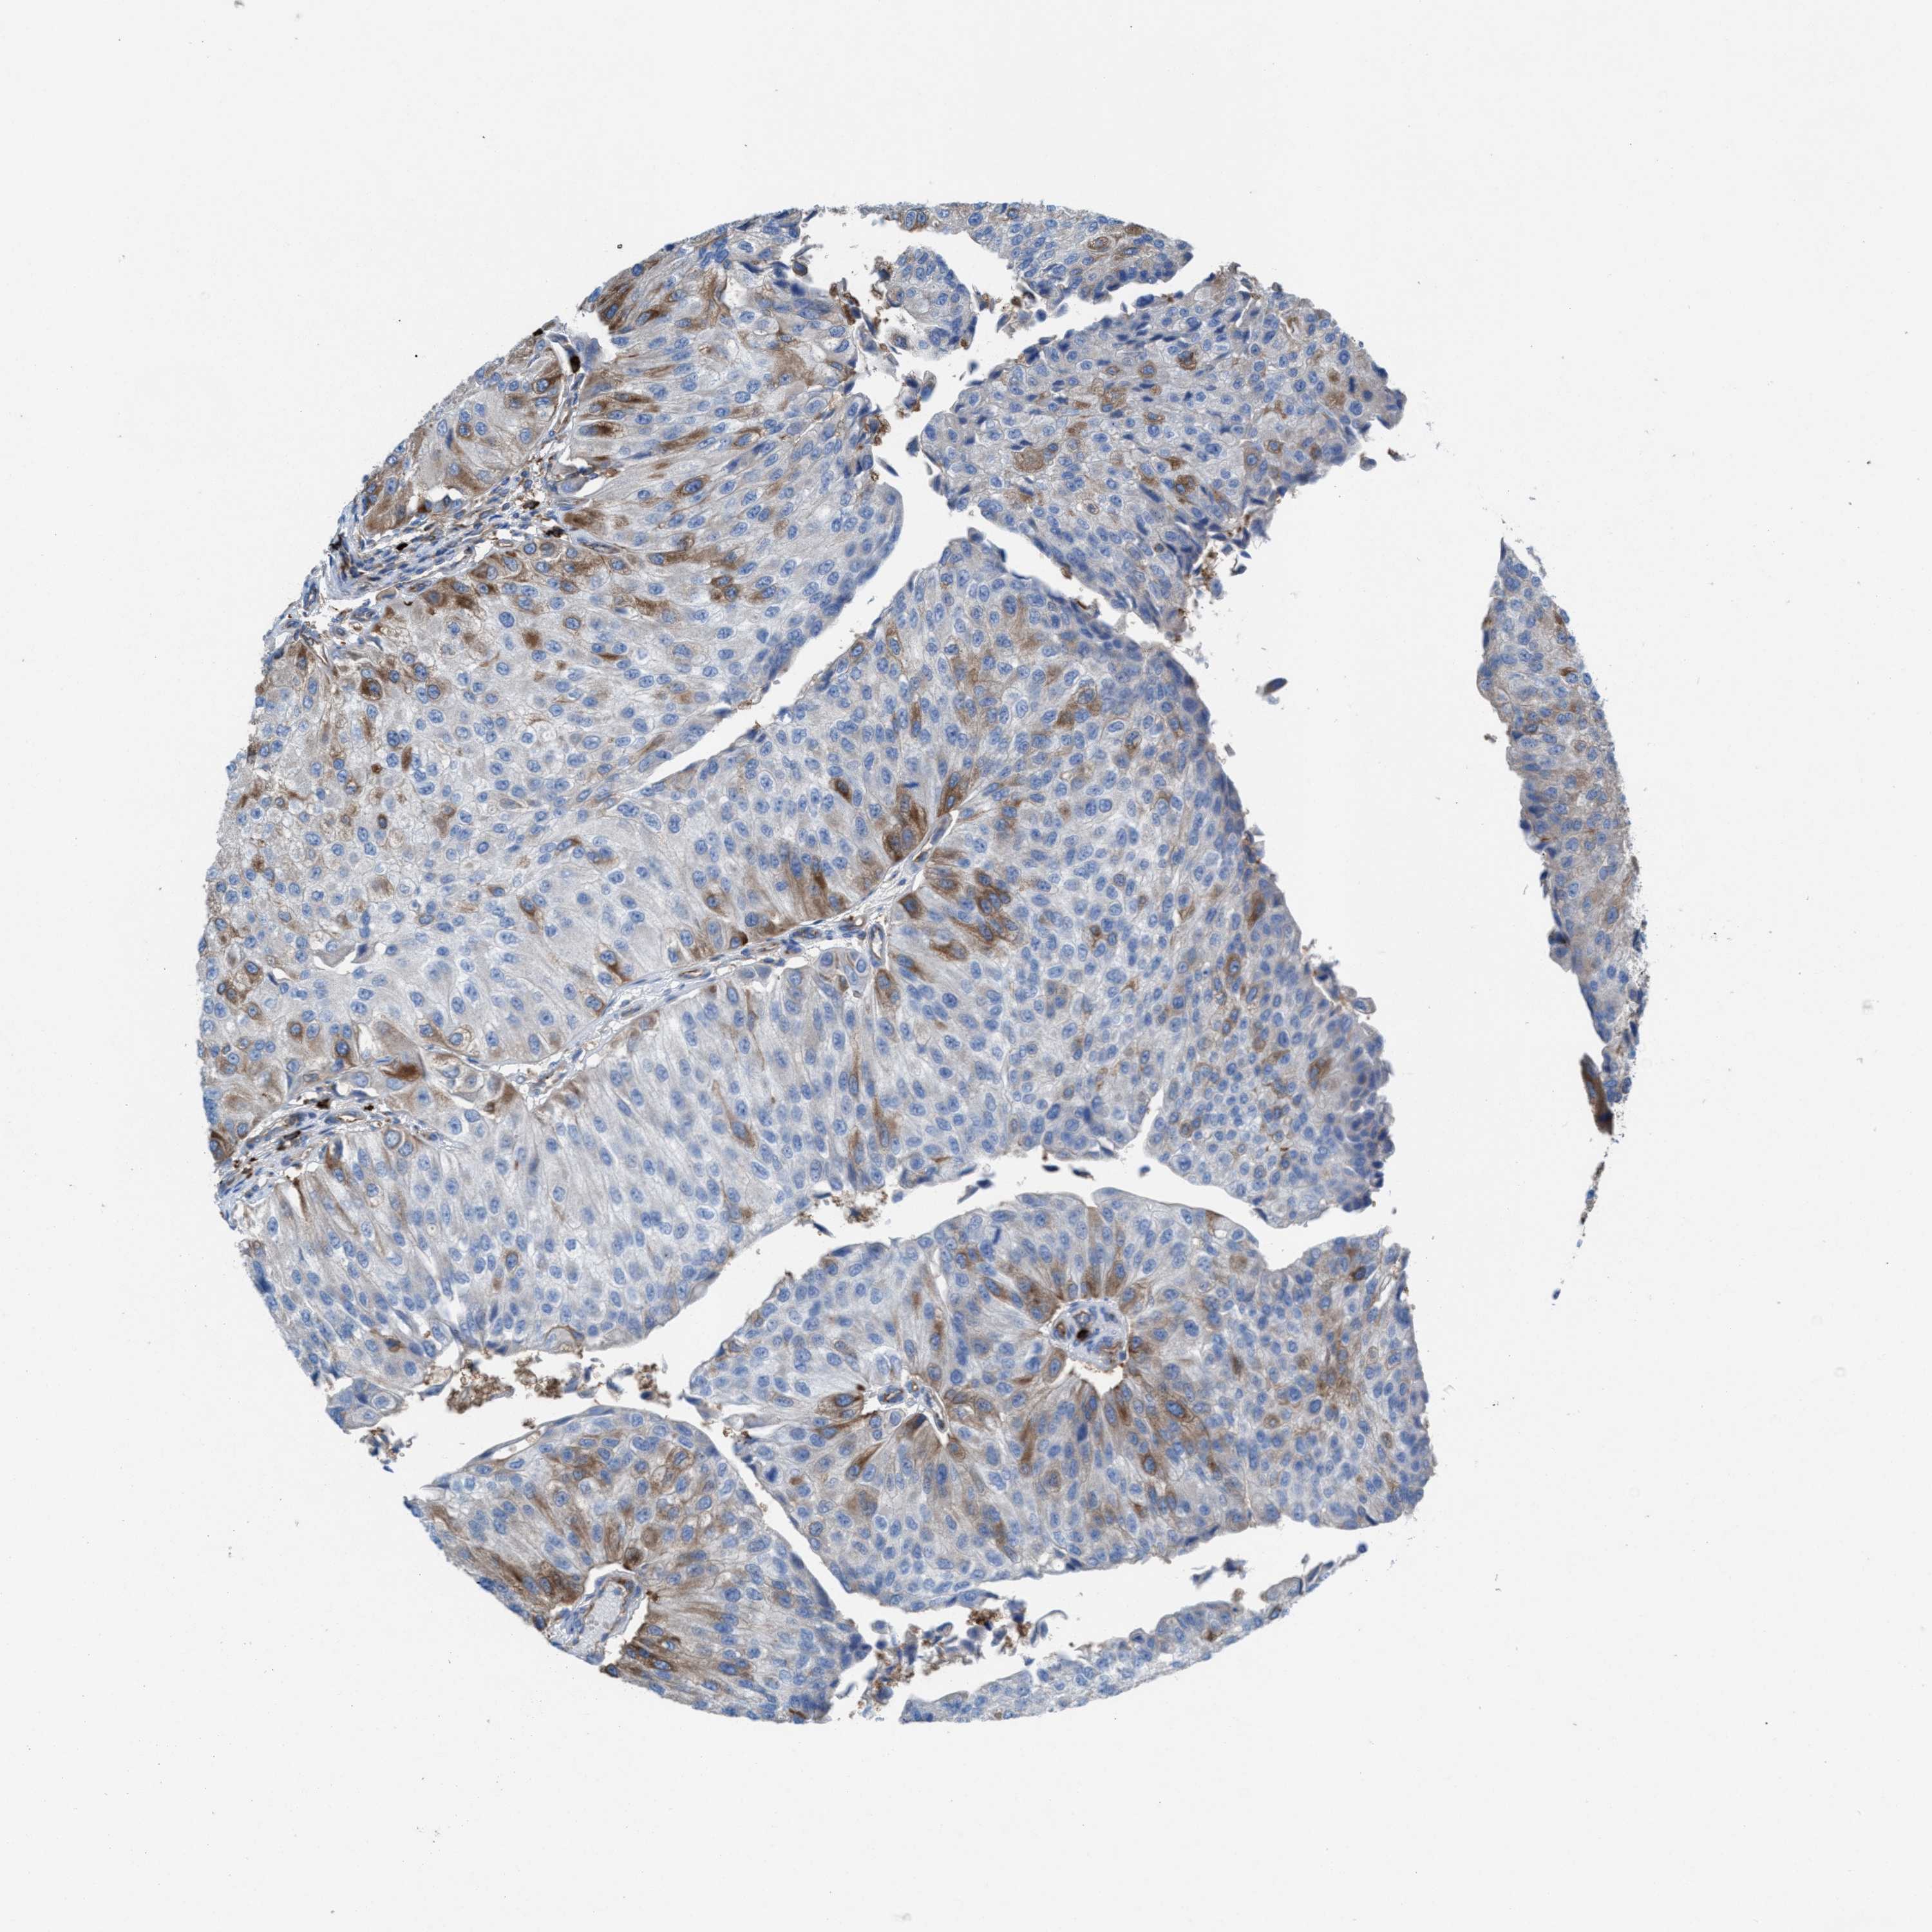

UROTHELIAL CANCER - Protein expressioni

A mouse-over function shows sample information and annotation data. Click on an image to view it in a full screen mode. Samples can be filtered based on level of antibody staining by selecting one or several of the following categories: high, medium, low and not detected. The assay and annotation is described here.

Antibody stainingi

Antibody staining in the annotated cell types in the current human tissue is reported as not detected, low, medium, or high, based on conventional immunohistochemistry profiling in selected tissues. This score is based on the combination of the staining intensity and fraction of stained cells.

Each image is clickable and will lead to virtual microscopy that enables deeper exploration of all samples and also displays staining intensity scores, fraction scores and subcellular localization as well as patient and tissue information for each sample.

Antibody HPA022251

Staining

High

Medium

Low

Not detected

Intensity

Strong

Moderate

Weak

Negative

Quantity

>75%

75%-25%

<25%

None

Location

Nuclear

Cytoplasmic/membranous

Cytoplasmic/membranous,nuclear

Urothelial carcinoma, Low grade